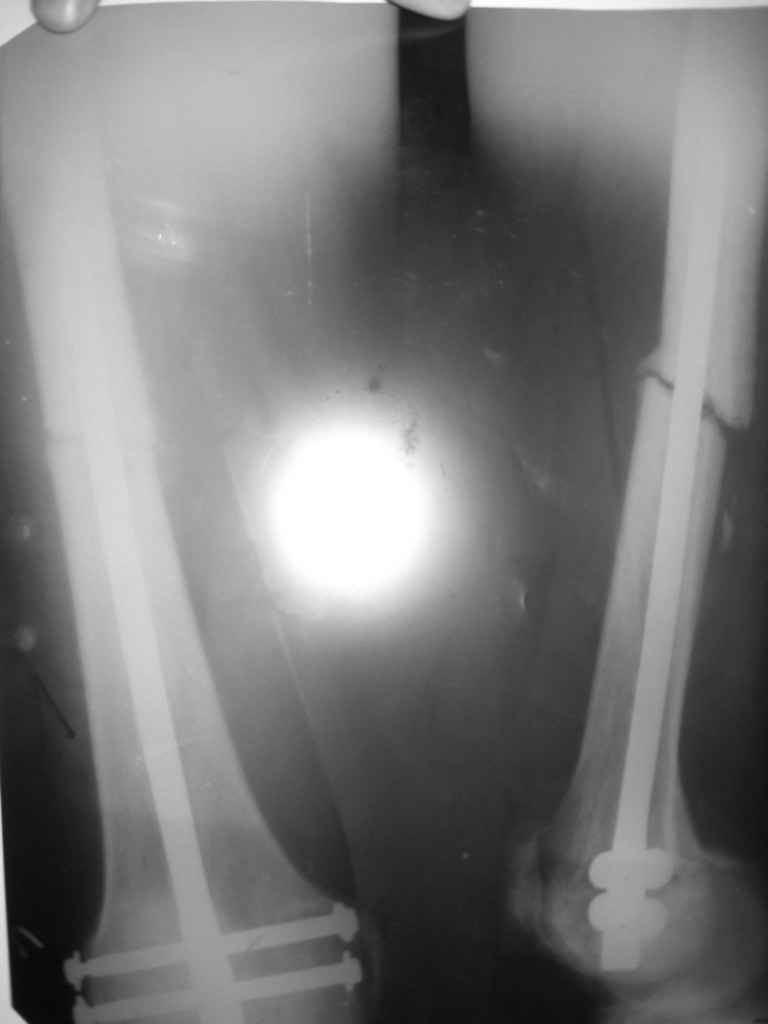

Уважаемые коллеги,обращаюсь к Вам за советом о дальнейшей тактие. Пециент был представлен к Вашему вниманию 28 октября 2008 года. В декабре пациенту была выполнена динамизация стержня удален винт из круглого отверстия).В данный момент ( прошло 2 мес. с момента динамизации)наблюдается диастаз в месте перелома и замедленная консолидация. Есть несколько мнений по дальнейшей тактике: 1 убирать второй винт из овального отверстия и нагрузка,но не произойдет ротационное смещение в данном случае? 2 Переставить винт в "овальном отверстии" выше , что бы исключить "ротацию", но не произойдет ли синание кортикального слоя вблизи отверстия от удаленного ранее винта? 3 Дать долную нагрузку,и терапию направленную на стимуляцию остеорегенерацию и посмотреть динамику,но не поломается ли винт в овальном отверстии? Снимки прилагаются.

Вы не показали проксимальный конец стержня на снимке. Если динамический винт уперся в нижний край овального отверстия. т.е. стал статическим, его целесообразно сразу убрать. Ротационного смещения я бы не опасался.

Уважаемый Петр! Данная ситуация вскорее всего связано со статистическим режимом блокировки динамического винта.

Я тоже разделяю мнение Александра Николаевича! оптимальным будет реостеосинтез в динамическом режиме. Представленная рентгенологическая картина характерна для нестабильного остеосинтеза, в связи с которой отмечается замделенная консолидация. В данном случае способом воздействия служит рассверливание к/канала и стабильный остеосинтез с ранней опорной нагрузкой. С уважением Ерсин Жунусов.

Перелом не сростается из за наличия диастаза. Для этого необходимо удалить второй винт и дать нагрузку наконечность. Наличие микроподвижности будет стимулировать остеогенез.Ротационнного смещения не будет потому что перелом косой и расположен в диафизе, где происходит полное облегание стержня кортикальным слоем.

Причины образования ложного сустава на бедре могут быть из-за отсутствия нагрузки по причине наличия другого перелома на том же сегменте, а также из-за несостоятельности конструкции, и ее малого диаметра, или когда гвоздь забивался без рассверливания канала.

Ожидаемый эффект микроподвижности без образования мозоли ускорит процесс перелома гвоздя.

При отсутствии эффекта от динамизации, и если прошло более 4 месяцев, это означает переход из замедленно срастающегося в стадию ложного сустава.

Более массивный гвоздь создаст стабильность, а рассверливание канала стимуляцию процесса.